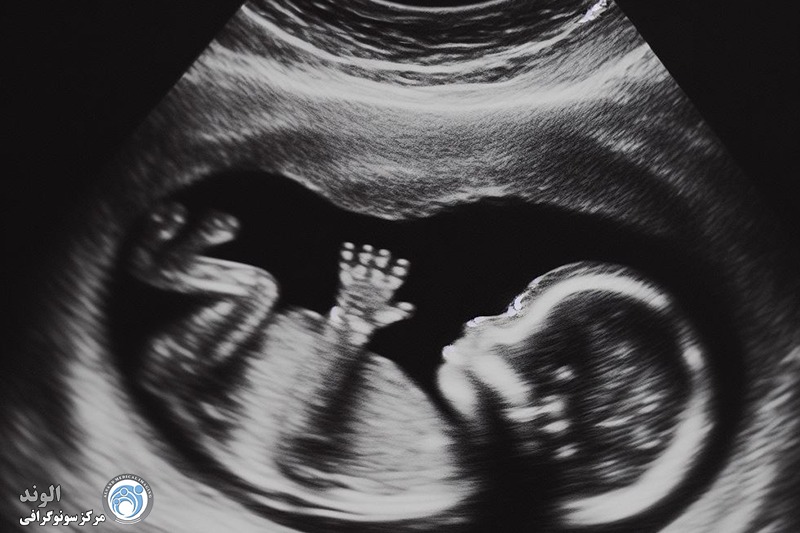

بین 17 تا 22 هفته، ما اغلب یک ارزیابی سونوگرافی از جنین انجام می دهیم تا آناتومی آن را از نزدیک ببینیم. این اسکن می تواند به ما بگوید که آیا مغز به درستی رشد کرده است، آیا شکاف لب، ناهنجاری قلبی و البته جنسیت جنین وجود دارد یا خیر.

آنومالی اسکن یا سونوگرافی سطح دوم، یک بررسی دقیق از آناتومی جنین است که معمولاً بین هفتههای ۱۸ تا ۲۲ بارداری انجام میشود. در این مرحله از رشد جنین، بسیاری از اندامها به اندازهای رشد کردهاند که میتوان ساختار آنها را به وضوح مشاهده و بررسی کرد. این سونوگرافی برخلاف اسکنهای اولیه که بیشتر برای تعیین سن بارداری یا بررسی ضربان قلب انجام میشوند، تمرکز اصلیاش بر شناسایی ناهنجاریهای ساختاری در جنین است.

اندامها: بررسی دستها، پاها و انگشتان.